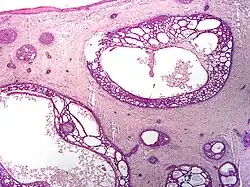

| Cystic basal-cell carcinoma | Morphologically characterized by dome-shaped, blue-gray cystic nodules.[31]: 647 |

| |